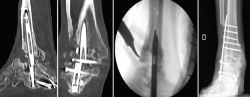

El paciente siguió una evolución favorable hasta un mes antes del control al año de la intervención donde, en la TAC solicitada, se objetivó ausencia de consolidación a nivel tibiotalar y subtalar con rotura del clavo.

Se reintervino al paciente realizando la extracción del fragmento distal del clavo sin dificultad. Para la extracción del fragmento proximal, se practicó, como en el caso anterior, además de la utilización de las guías curvadas, en el foco de pseudoartrosis, una muesca en el clavo con la fresa de alta velocidad para apoyar el escoplo. De ese modo, con la ayuda de la percusión directa sobre el clavo, se consiguió la extracción del extremo proximal a través de la planta del pie. Tras legrar las superficies articulares y aportar injerto tricortical de cresta ilíaca, se realizó la fijación con una placa de artrodesis TTC (Palex Medical) (Figura 5).

Figura 5. Imágenes de tomografía computarizada con el clavo roto. Finalización de la extracción con la guía curvada a través de la luz del clavo. Rescate con placa tibiotalocalcánea e injerto corticoesponjoso colocado en el foco.